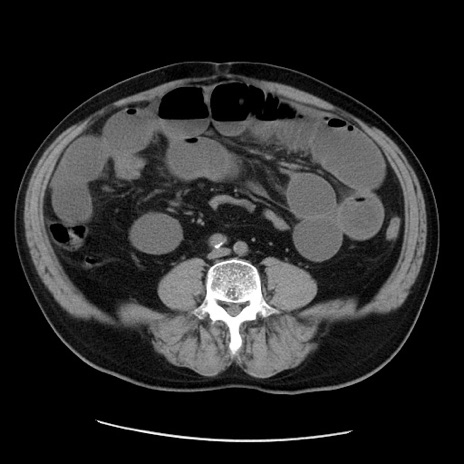

症例20(横断像)

【症例】 60歳代男性

【主訴】 腹部膨満、嘔吐

【現病歴】5日前頃より倦怠感を認め食事量減少し4日前の朝嘔吐、食事摂取困難となった。 3日前近医受診し点滴施行され整腸剤などを処方された。 当日他院を受診し、腹部膨満著明、炎症反応の上昇(CRP10.8、WBC11200)あり、紹介受診となる。

【身体所見】 意識JCS1 受け答えがはっきりしないBP 111/57mHg、 P 67bpm、、BT35.2°C、SpO2 97%(RA)、 腹部:膨隆、打診で鼓音あり、全体的に圧痛有り、腸蠕動音(-)、反跳痛ははっきりせず。

【データ】WBC 11400、CRP 14.20